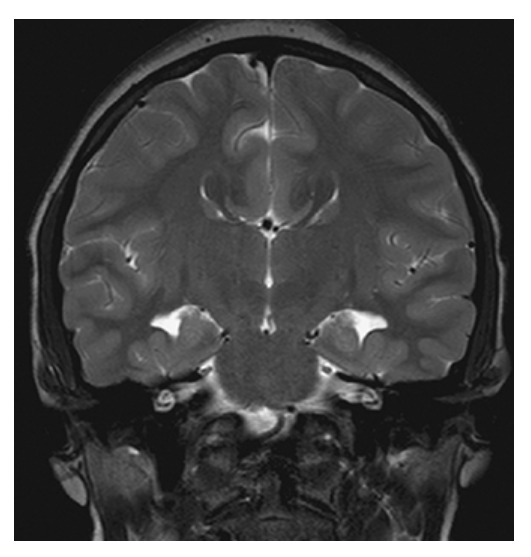

Agenesis of the Corpus Callosum. Coronal T2W image shows agenesis of the corpus callosum with widely spaced lateral ventricle and continuity of the third ventricle with the interhemispheric fissure.